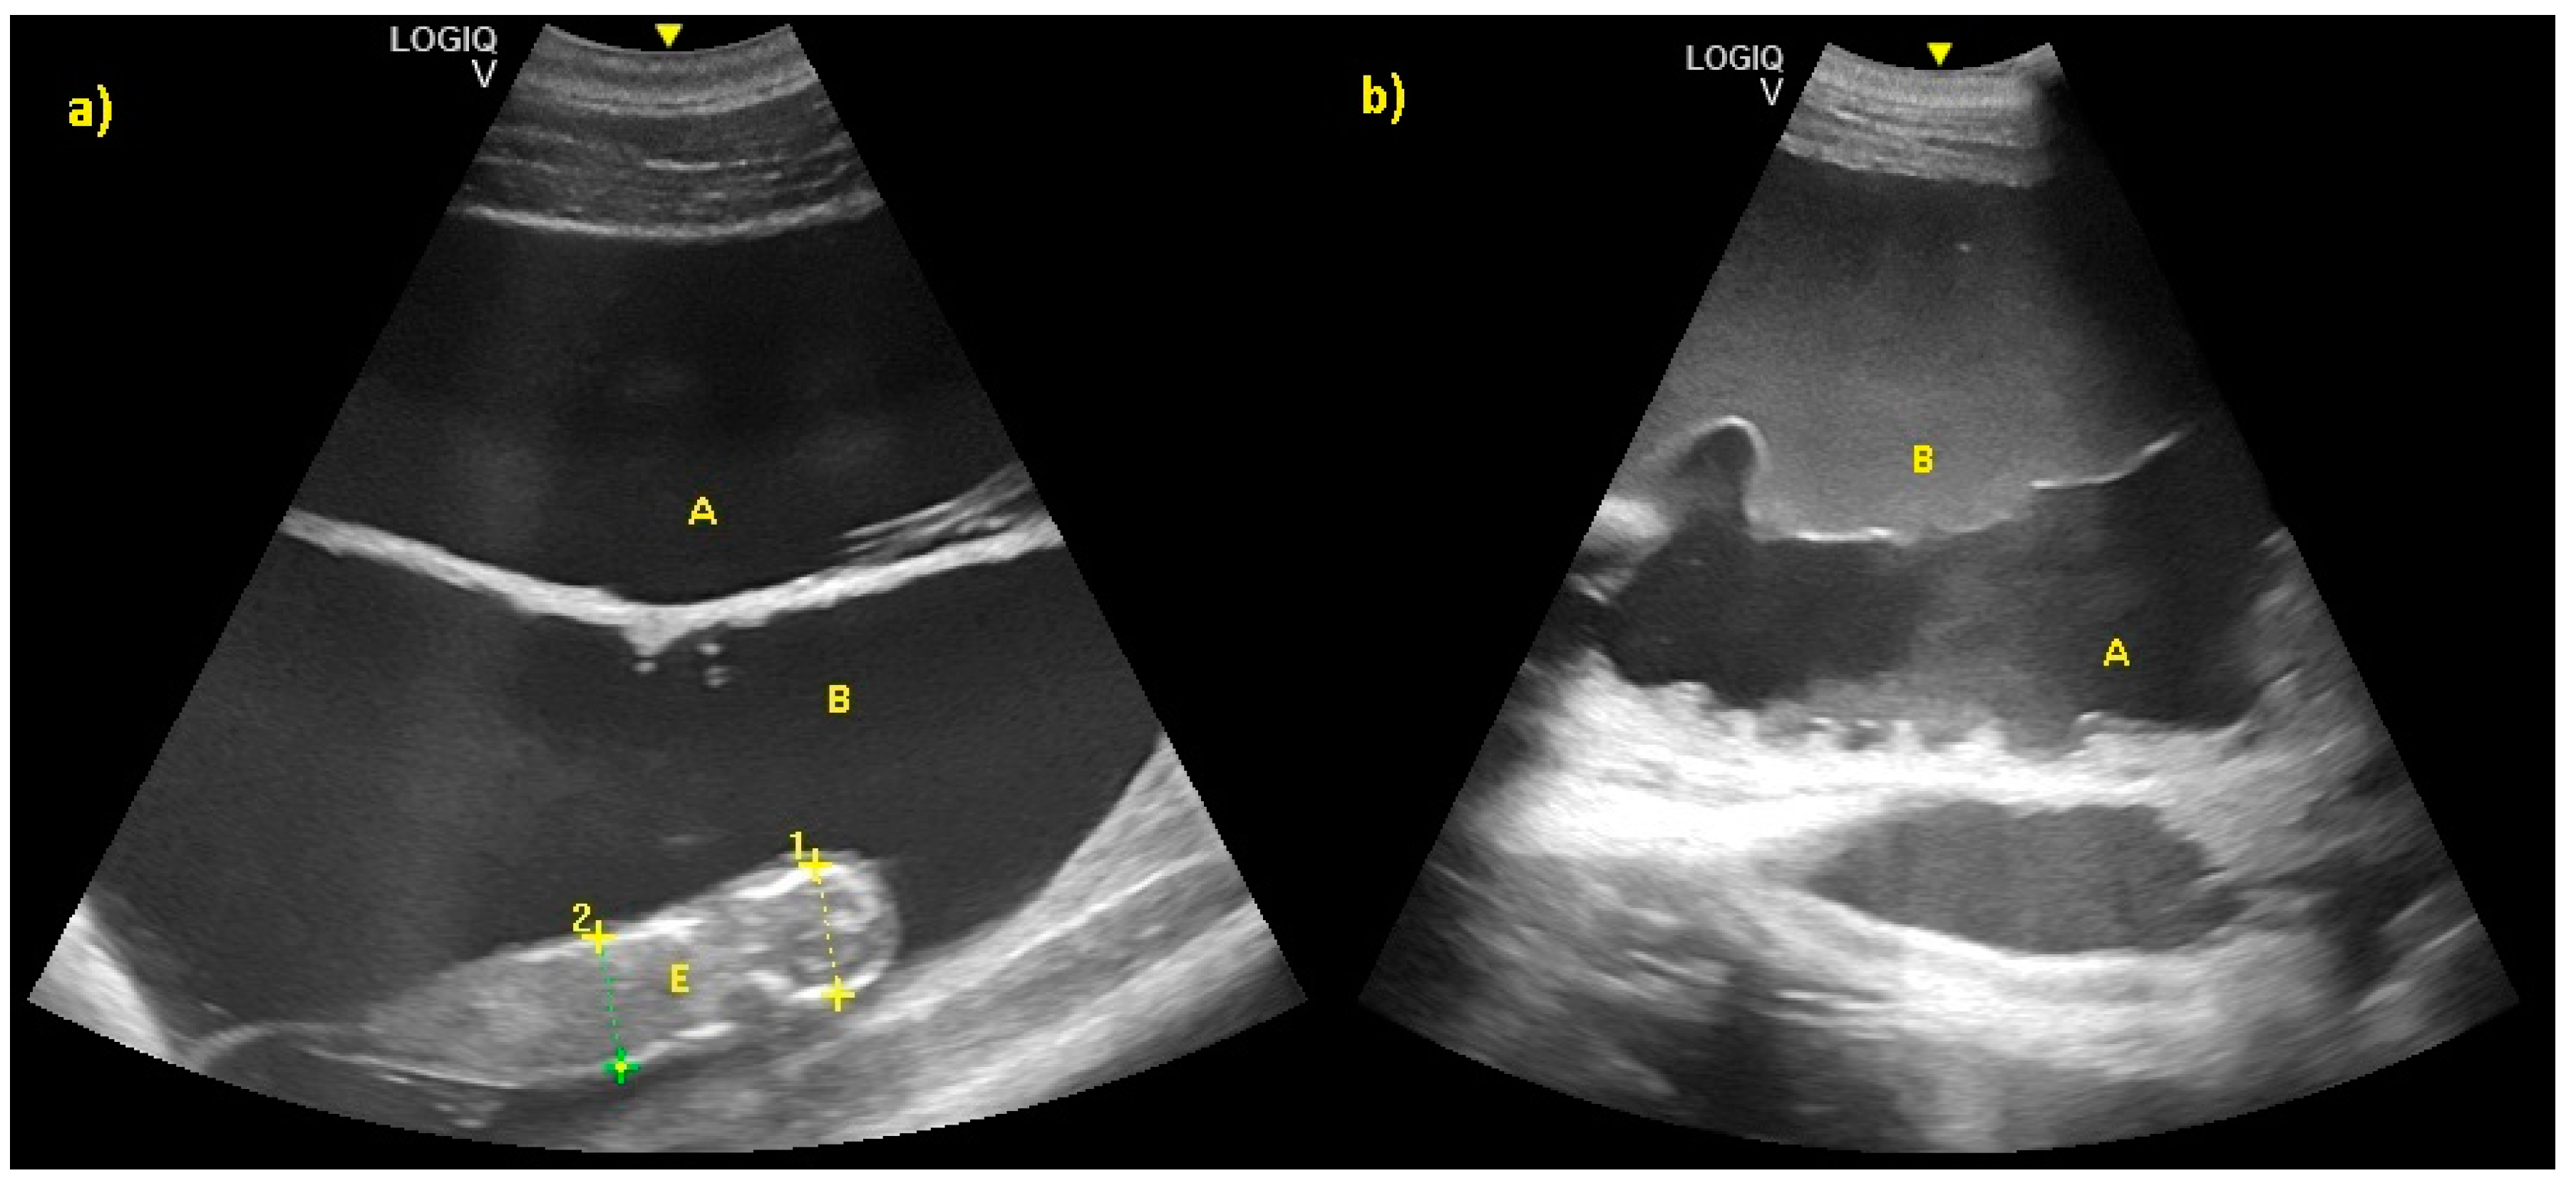

Allantoic and amniotic fluid are distinguishable in all examinations starting from the last trimester of pregnancy. Allantoic fluid appears as an anechoic fluid and the amniotic fluid appears as a hyper-echoic fluid, with an increasing number of echoic particles during the last period of pregnancy (Figure 11).

Figure 11.

(a) Allantoic (A) and amniotic fluid (B) in early stage of pregnancy. (b) Allantoic fluid appears as an anechoic fluid (A), and the amniotic fluid appears as a hyper-echoic fluid, with an increasing amount of echoic particles during the last period of pregnancy (B).